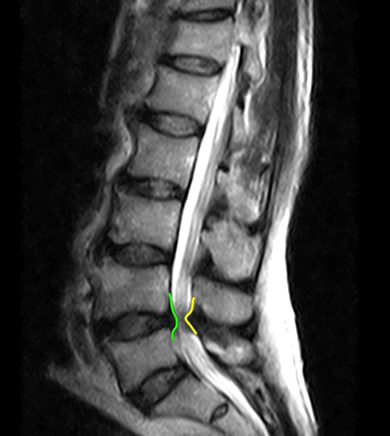

Đại cương Do những cấu trúc xung quanh của đĩa đệm cũng bị ảnh hưởng nên thuật ngữ bệnh lý thoái hóa cột sống(degenerative spine disease) thích hợp hơn thuật ngữ bệnh lý thoái hóa đĩa đệm (disc degenerative disease). Spondylosis là một thuật ngữ không đặc hiệu, nó có thể bao gồm cả bệnh lý thoái hóa cột sống. Bệnh lý thoái hóa cột sống là một quá trình […]